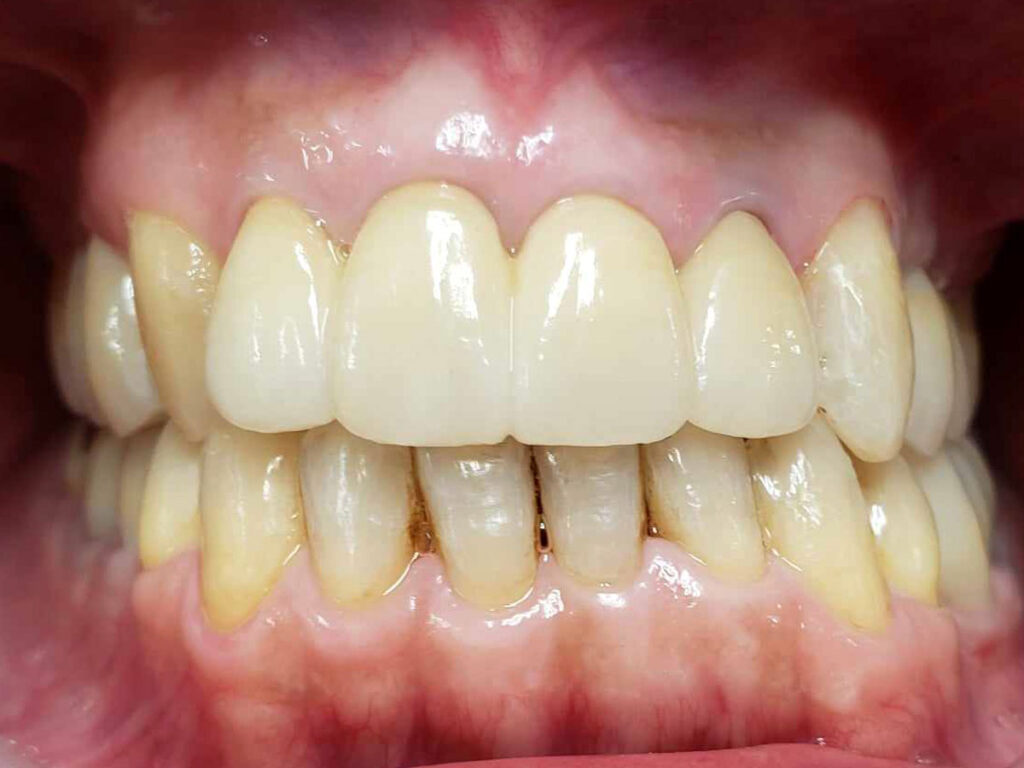

術後

治療期間は約3年でした。本来、外科矯正も視野にいれた方が良いかもしれない、ウルトラE難度のケースだったと思います。しかし年齢的な問題、歯の問題も解決しないといけないため、歯並びは治っても骨格的な問題は解決できないと患者さんに最初に説明してから治療に入りました。しかし、本人最終的な仕上がりには大変満足しているようです。

更に化膿していた歯根も全て当医院の再治療で完治したことがCT画像でもわかるため、大変感謝されました。ただ、本来アレルギー体質も考慮して、全てメタルフリーという考えもありましたが、問題ない銀歯を触り神経の処置が必要になるリスクも考慮して、そのまま経過観察とさせて頂きました。また、咬合負担のかかり側方圧のかかりやすい親知らずの修復にはゴールド修復を行いました。いずれ皮膚科に金属アレルギーの検査に行ってもらい、陽性反応がでればやり直す予定ですが、再修復に関しましては自費料金を割り引こうと考えています。

今後、4か月メンテナンスを行い、良好な口腔内を保ってほしいと思っていますが、口腔内管理がバッチリのため、歯周病に関しては全く心配していません。寧ろ、無理な力がかかったときの歯根の破折や根っこの化膿の再発が心配ですかね。しかし、この歯磨き良好なカリエスパワータイプ(虫歯、力)は、歯並びや噛み合わせが良ければ、次にインプラントに移行したとしても、良い予後は約束されていることも今の段階でもわかります。